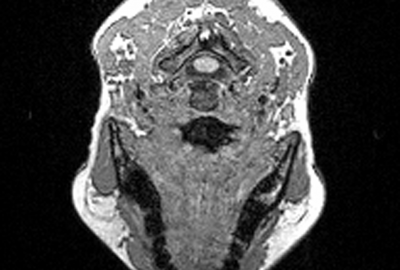

- Muscle-based facial animation considering fat layer structure captured by MRI

Muscle-based facial animation [Lee et al. 1995] is one of the best approaches to realize facial expressions of characters. However, this approach does not consider the personal variation in facial tissue model such as skin thickness. So personal character in emotional expression can not be reflected in this model.